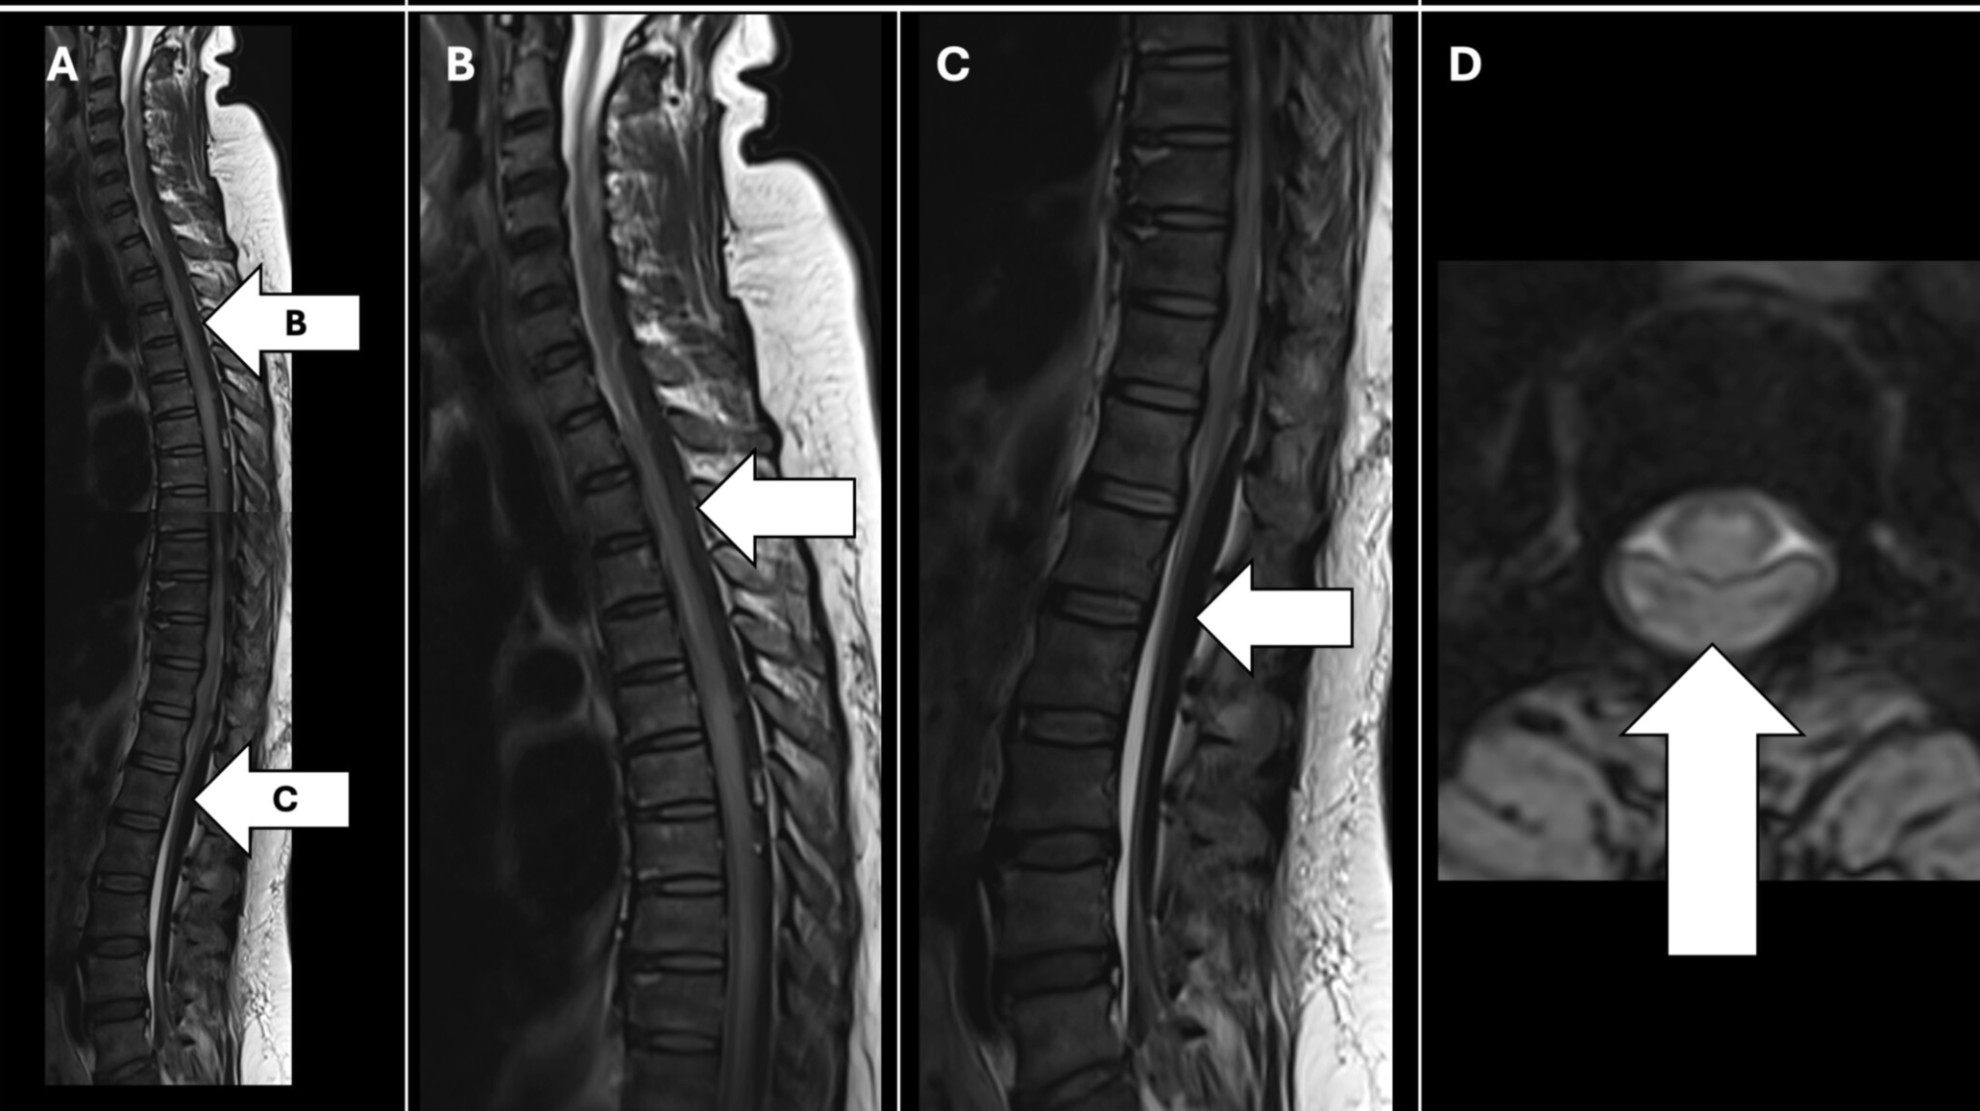

Из-за головной боли пациентке выполнили МРТ. Исследование показало массивное кровоизлияние в спинной мозг, протянувшееся от С4 до С1 и вызвавшее компрессию спинного мозга. КТ головы показала кровоизлияние в левую лобную долю головного мозга. Оно не сопровождалось выраженными очаговыми неврологическими симптомами. Ранее не сообщалось о случаях одновременного внутричерепного и спинномозгового кровоизлияния после внутривенного введения тенектеплазы.